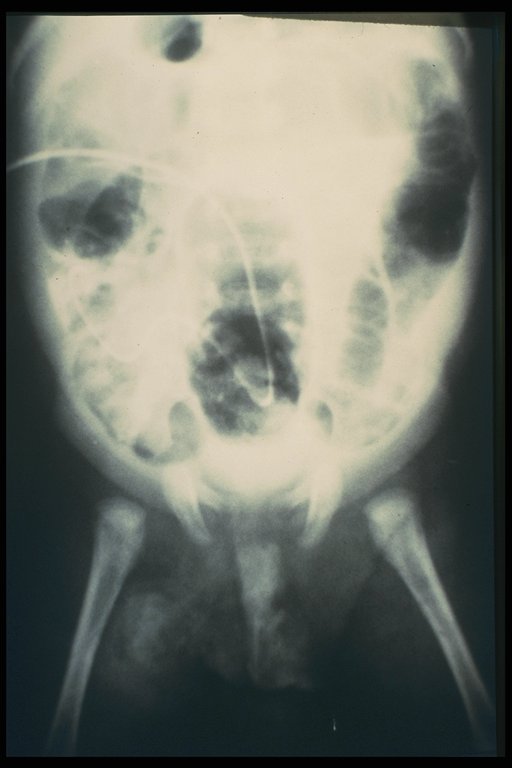

Plain X-ray shows the catheter inside the peritoneal cavity

Contrast filled through the catheter into the intestine - patent vitelline duct

Fistulogram demonstrated the tract connected between the umbilicus and the intestine